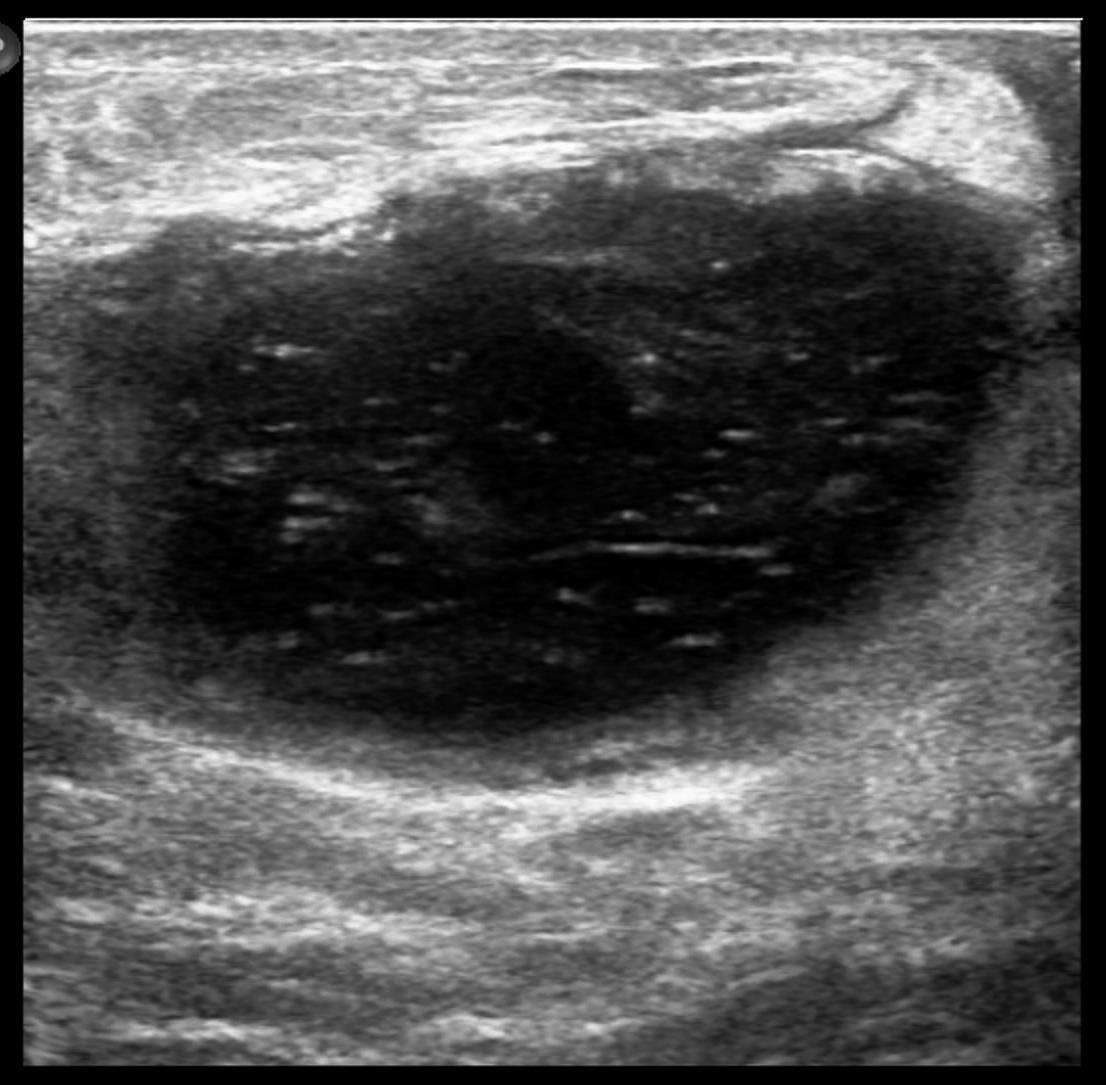

Ultrasound showed at 12 o’clock position in retroareolar region, a complicated cyst with thick nodular wall measuring 4.4x3.1x5.0 cm. Right axilla showed two round LN with effaced hila measuring 0.6 cm.

Ultrasound commonly shows irregular hypoechoic confluent mass with tubular extensions, circumscribed hypoechoic mass, skin thickening and edema with axillary lymphadenopathy having reactive features. Less common features include heterogeneous hypoechoic confluent masses with indistinct, lobulated or angular margins, parenchymal distortion with no discrete masses and heterogeneous parenchyma with edema. The lesions and surroundings show increased vascularity. The findings will be normal in 4-20% of the cases. With advanced disease, fluid collections or abscesses may be present.

Core biopsy was performed that showed granulomatous mastitis with focal suppuration. Special stains were negative for AFB and fungi. Fine needle aspiration cytology of the axillary lymph nodes also showed reactive cytology.